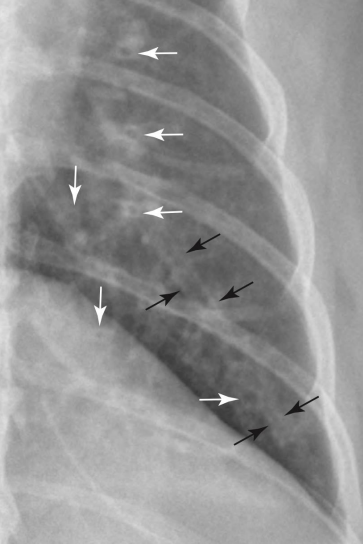

Alveolar pattern

• ์–ธ์ œ?

• ๋ฌด๊ธฐํ, ํ๋ ด,. .

• ์ƒ๋ช…๊ณผ ๊ด€๋ จ ์žˆ๋Š” ์งˆ๋ณ‘๊ณผ ๋ฐ€์ ‘ํ•˜์—ฌ, ๊ฐ€์žฅ ์ค‘์š”

• perihilar region์—์„œ pattern

• ๊ณ ์–‘์ด : ์ „๋ฐ˜์ ์œผ๋กœ ์ง€์ €๋ถ„ํ•˜๊ฒŒ ์ฐฌ ๋ชจ์Šต

• ๊ณ ์–‘์ด ํ์ˆ˜์ข…์˜ ์ „ํ˜•์  : ์ข€ ์ง€์ €๋ถ„ํ•˜๊ฒŒ ๋‚˜ํƒ€๋‚จ, ๋‹ค๋ฅธ ํŒจํ„ด๊ณผ ํ—ท๊ฐˆ๋ฆผ

• ํ๊ฐ€ ์ชผ๊ธ€์–ด๋“ค์–ด

• ์˜ค์—ฐ์„ฑ ํ๋ ด (